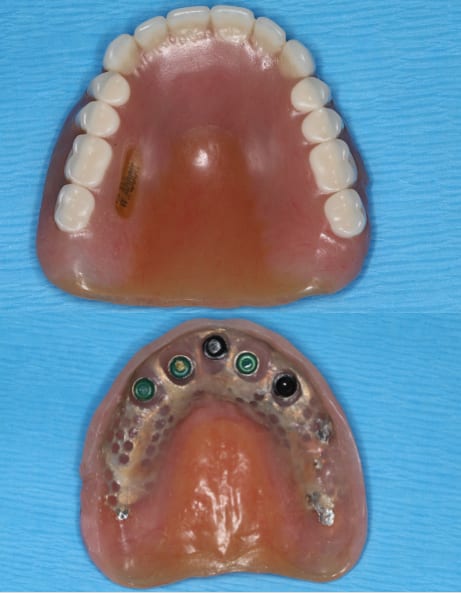

A polymethyl methacrylate (PMMA) appliance was verified for occlusion and esthetics (Figure 10). Once esthetics were evaluated and approved the final LOCATOR FIXED® prosthesis was processed in BruxZir zirconia (Glidewell). The black laboratory procession attachments were removed and replaced with the appropriate final LOCATOR FIXED® insert (Figure 11). The LOCATOR abutments and processing attachments are illustrated in Figure 12, which shows the tools for seating and removing the proprietary inserts and the insertion and removal tools. Proper inserts were selected and positioned per the manufacturer’s instructions (Figure 13). The final zirconia fixed prosthesis was seated using the seating tool and evaluated for stability (Figure 14). The prosthesis allowed for minimal palatal coverage, and the functional and esthetic maxillary reconstruction was complete (Figure 15 and Figure 16).